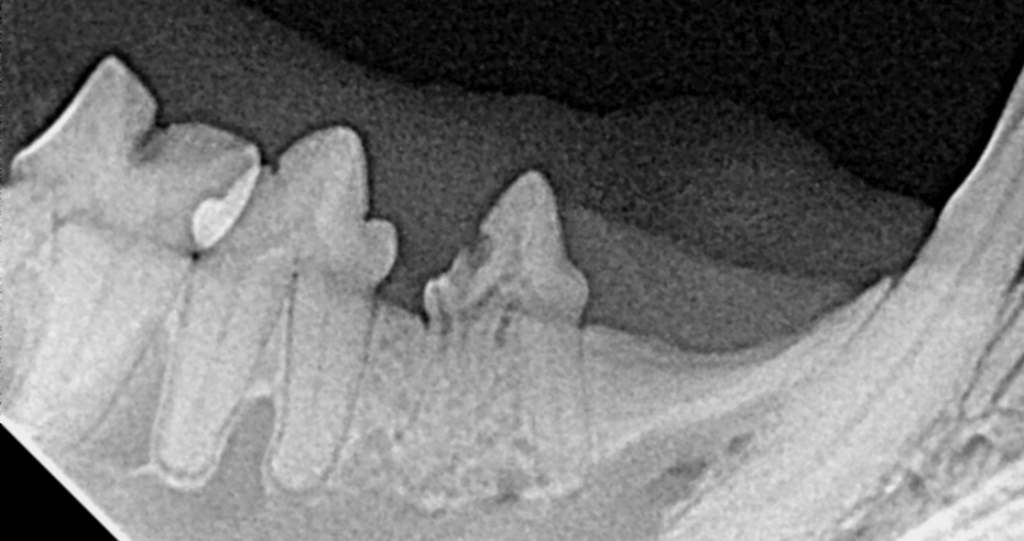

The x-ray of this site under anesthesia:

Revealing a focal ‘black’ spot of tooth (inflammatory tooth resorption) and loss of architecture of the root on the left (replacement resorption). A modified extraction technique (MET) can be used for the root on the left so that the remaining parts are below the gingival margin, but the root on the right must be removed in entirely or will continue to cause problems. Fragments of roots not having replacement resorption (aka retained tooth roots (RTR)) will not resorb. Tooth resorption is a painful often hidden disease usually happening along with periodontal disease. It is important to ensure your veterinarian uses intraoral radiographs or detailed 3D imaging for all cat dental procedures, as TR is not confined to the crown, but in fact, is a generalized recurring process. As stated above, due to the increased incidence of tooth resorption when inflammation is present, when you treat TR through extraction of teeth you slow the recurrence.